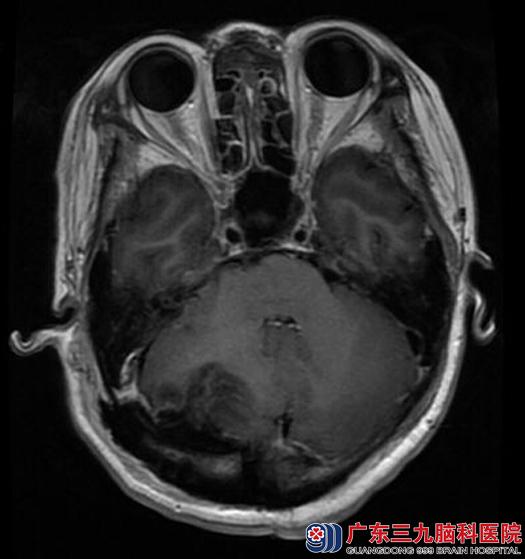

完善相关检查后,由综合神经外科鲁明主任主刀,在全麻下行右侧小脑幕下镰窦旁脑膜瘤切除术,术中见右侧天幕下灰白色肿瘤组织,肿瘤边界较清,血供丰富,质软,予显微镜下分块切除,肿瘤基底部位于右侧小脑幕下,侵犯右侧横窦,予切除横窦内肿瘤组织,镜下全切肿瘤,手术顺利。术后,陈女士头痛症状明显好转,已康复出院。术后病理结果:过渡型脑膜瘤。

手术后